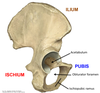

1? 2? 3?

Green arrow?

3? 4?

3? 4? 5?